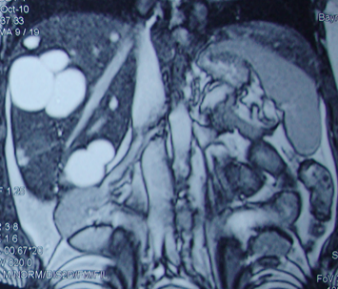

PVT diaqnozunu dəqiqləşdirmək üçün portoqrafiya aparılır – Doppler USM, KT və ya MRT angioqrafiya.

- Kontrastlı müayinələrdə damarda tromb və ya kavernoz transformasiya

Portal vena trombozu qapı venasının özünün və ya böyük şaxələrinin trombotik tıxanmasıdır, durğunluq, trombofiliya və tibbi müdaxilələr ən çox rast gəlinən səbəbləridir. Yerinə görə 4 forması var: ana portal vena (ekstrahepatik), intrahepatik şaxə, dalaq venası və çöz venası. Ekstrahepatik formanın kəskin fazası (tromboz) kəskin hepatit, xroniki fazası (kaverna) isə PH əlamətləri ilə büruzə verir. İntrahepatik formada qaraciyər nekrozu meydana gəlir. Dalaq venası trombozunda splenomeqaliya, hipersplenizm və fundal varikozlar baş verir, çöz venası trombozu bağırsaq qanqrenasına səbəb olur. Diaqnozunu təyin etmək üçün kontrastlı müayinələr lazım gəlir, damarda trombun və ya kavernoz transformasiyanın görünməsi diaqnozu dəqiqləşdirir. Ekstrahepatik formada antikoaqulyant və PH müalicəsi, dalaq venası trombozunda splenektomiya, çöz venası trombozunda rezeksiya və embolektomiya, intrahepatik formada rezeksiya və ya transplantasiya gərəkə bilir.

- portoqrafiyada vena mənfəzində trombun görünməsi;

- venanın distalında genişlənmə və kavernoz transformasiyanın görünməsi;

- Portal hipertenziya, qaraciyər disfunksiyası və ya asimptomatik;

- Kontrastlı müayinələrdə damarda tromb və ya kavernoz transformasiya;